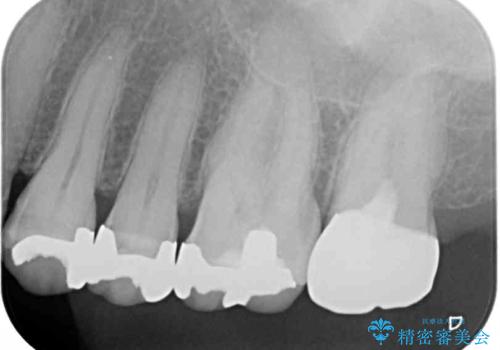

上顎の奥歯は神経にまで虫歯が及んでいる可能性が高かったため、抜髄や断髄の可能性を考慮しながら処置を進め、セラミッククラウンにて補綴することとしました。

上の奥歯は一部神経を取り除くこととなりましたが、残った神経は正常な状態を保つことができました。

下の奥歯も、虫歯を取り除いて仮歯を装着したことで歯肉の腫れが引き、出血することもなくなりました。